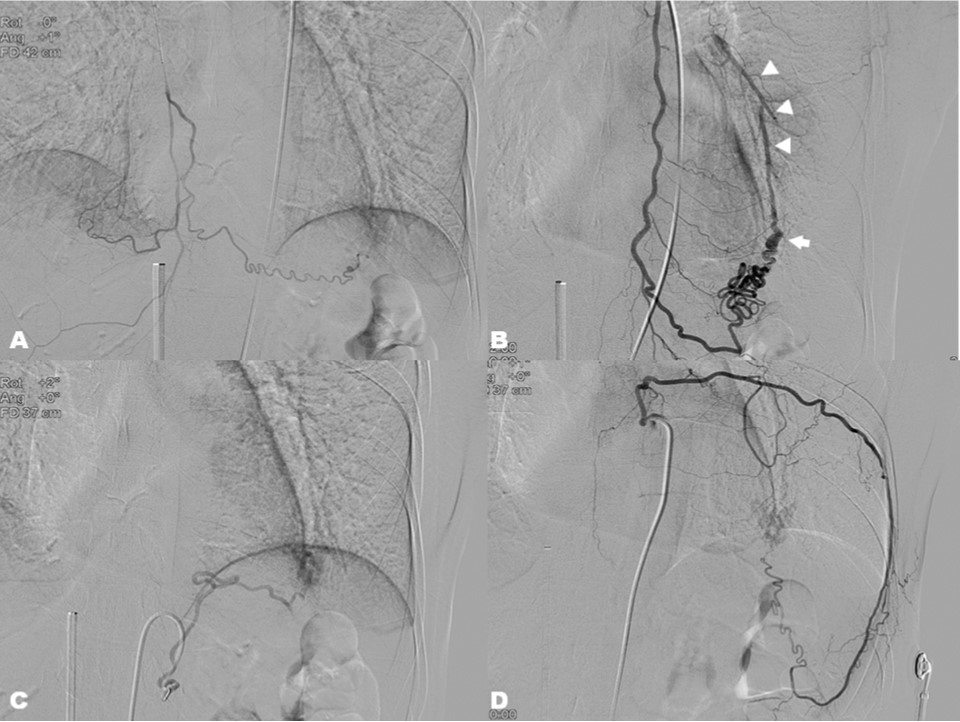

Fig. 2.

Selective angiographic for (A) right internal mammary artery, (B) left internal mammary artery, (C) left inferior phrenic artery, and (D) left 8th intercostal artery showed the fistulous connection to the malformed pulmonary artery (arrow) which is draining into lingular pulmonary artery (arrowheads).